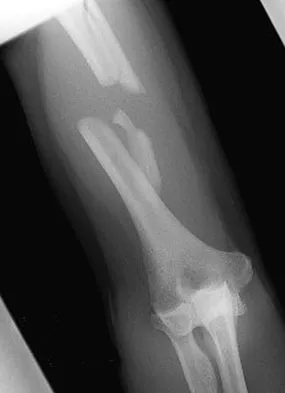

Figures 32a and 32b show the AP and lateral radiographs of an 11-year-old boy who has a severe limp, a fever, and swelling and tenderness of the thigh. Aspiration of the bone reveals purulent material. The patient has most likely been symptomatic for

Explanation

In patients with an osteomyelitic infection, radiographic findings at 1 to 5 days usually show soft-tissue swelling only. Seven to 14 days after symptoms begin, radiographs will most likely show the classic signs of acute osteomyelitis. Reactive bone formation would be expected by 6 months. Kasser JR (ed): Orthopaedic Knowledge Update 5. Rosemont, IL, American Academy of Orthopaedic Surgeons, 1996, pp 149-161.